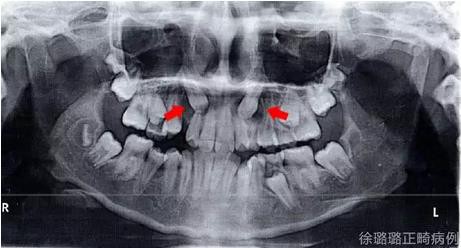

影像學(xué)檢查

X 線檢查:替牙列,上頜雙側(cè)尖牙埋伏阻生(含牙囊腫),四顆第三恒磨牙牙胚存在。

前牙 CT 檢查:上頜雙側(cè)尖牙埋伏阻生——雙側(cè)尖牙的牙冠均在側(cè)切牙根方的唇向位。